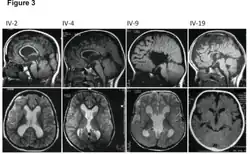

| MRI images showing megalencephaly in four family members who all have unusually large skulls (the family is affected by an autosomal recessive syndrome caused by a KIF7 mutation that induces multiple epiphyseal dysplasia)[1] | |

Megalencephaly (or macrencephaly; abbreviated MEG) is a growth development disorder in which the brain is abnormally large. It is characterized by a brain with an average weight that is 2.5 standard deviations above the mean of the general population.[2] Approximately 1 out of 50 children (2%) are said to have the characteristics of megalencephaly in the general population.[3]

A mutation in the PI3K-AKT pathway is believed to be the primary cause of brain proliferation and ultimately the root cause of megalencephaly. This mutation has produced a classification of brain overdevelopment that consists of two syndromes including megalencephaly-capillary malformation (MCAP) and megalencephaly-polydactyly-polymicrogyria-hydrocephalus (MPPH).[4] Megalencephaly is usually diagnosed at birth and is confirmed with an MRI.

A neurological exam will then be performed using the technology of an MRI machine in order to confirm the diagnosis of megalencephaly. These imaging tests give detailed information regarding brain size, volume asymmetry and other irregular developments linked with MCAP, MPPH and hemimegalencephaly.[2][21]